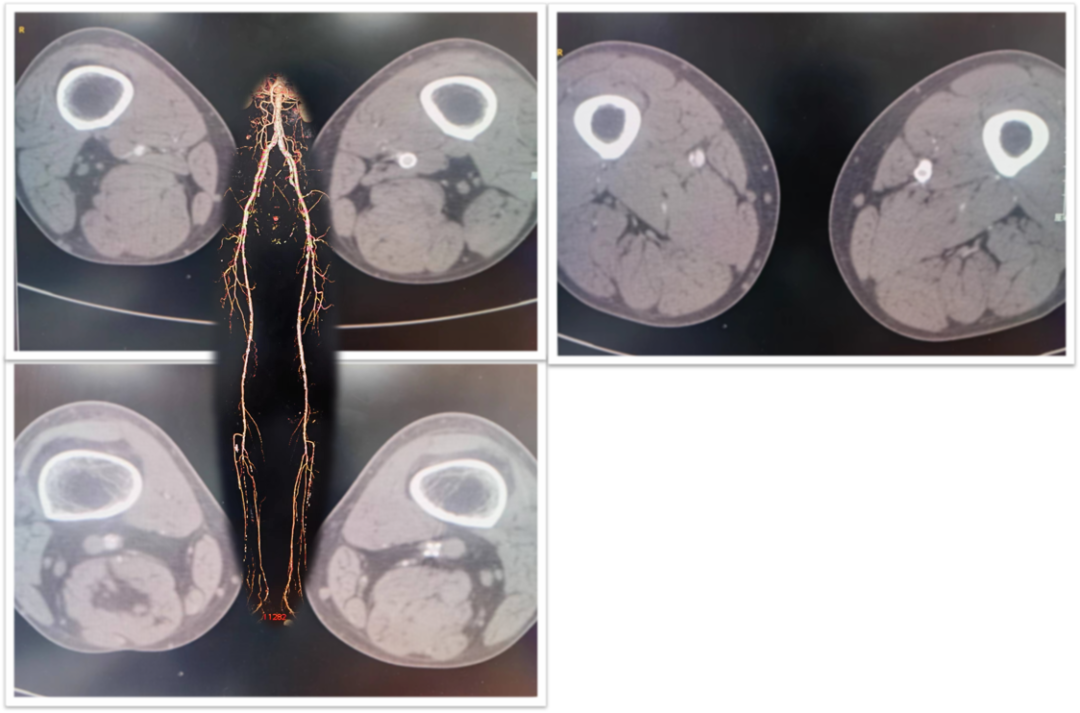

CTA:左侧股总动脉高钙化性偏心性严重狭窄病变,左股浅动脉及腘动脉全程弥漫性钙化病变,节段性狭窄,股浅动脉远段至腘动脉P1段完全闭塞,左侧胫前动脉至足背动脉闭塞

ABI:左侧0.37,右侧0.81

图为:术中造影评估 髂股段

图为:术中造影评估 膝下踝下段

根据PACSS 透视/DSA下钙化分级属于PACSS Grade 4C

图为:导丝通过病变 置入保护伞 使用Turbohawk定向旋切

图为:股腘动脉DAART+区域性DES 最终造影

图为:2023年11月 2年后复查

2年后(2023-11)复查

下肢动脉CTA提示左股腘动脉通畅,DES区域未见内膜增生管腔丢失表现